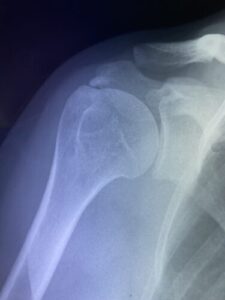

骨折・脱臼

肩関節脱臼の整復と痛みの緩和:牛久市の蛯原接骨院におけるアプローチ